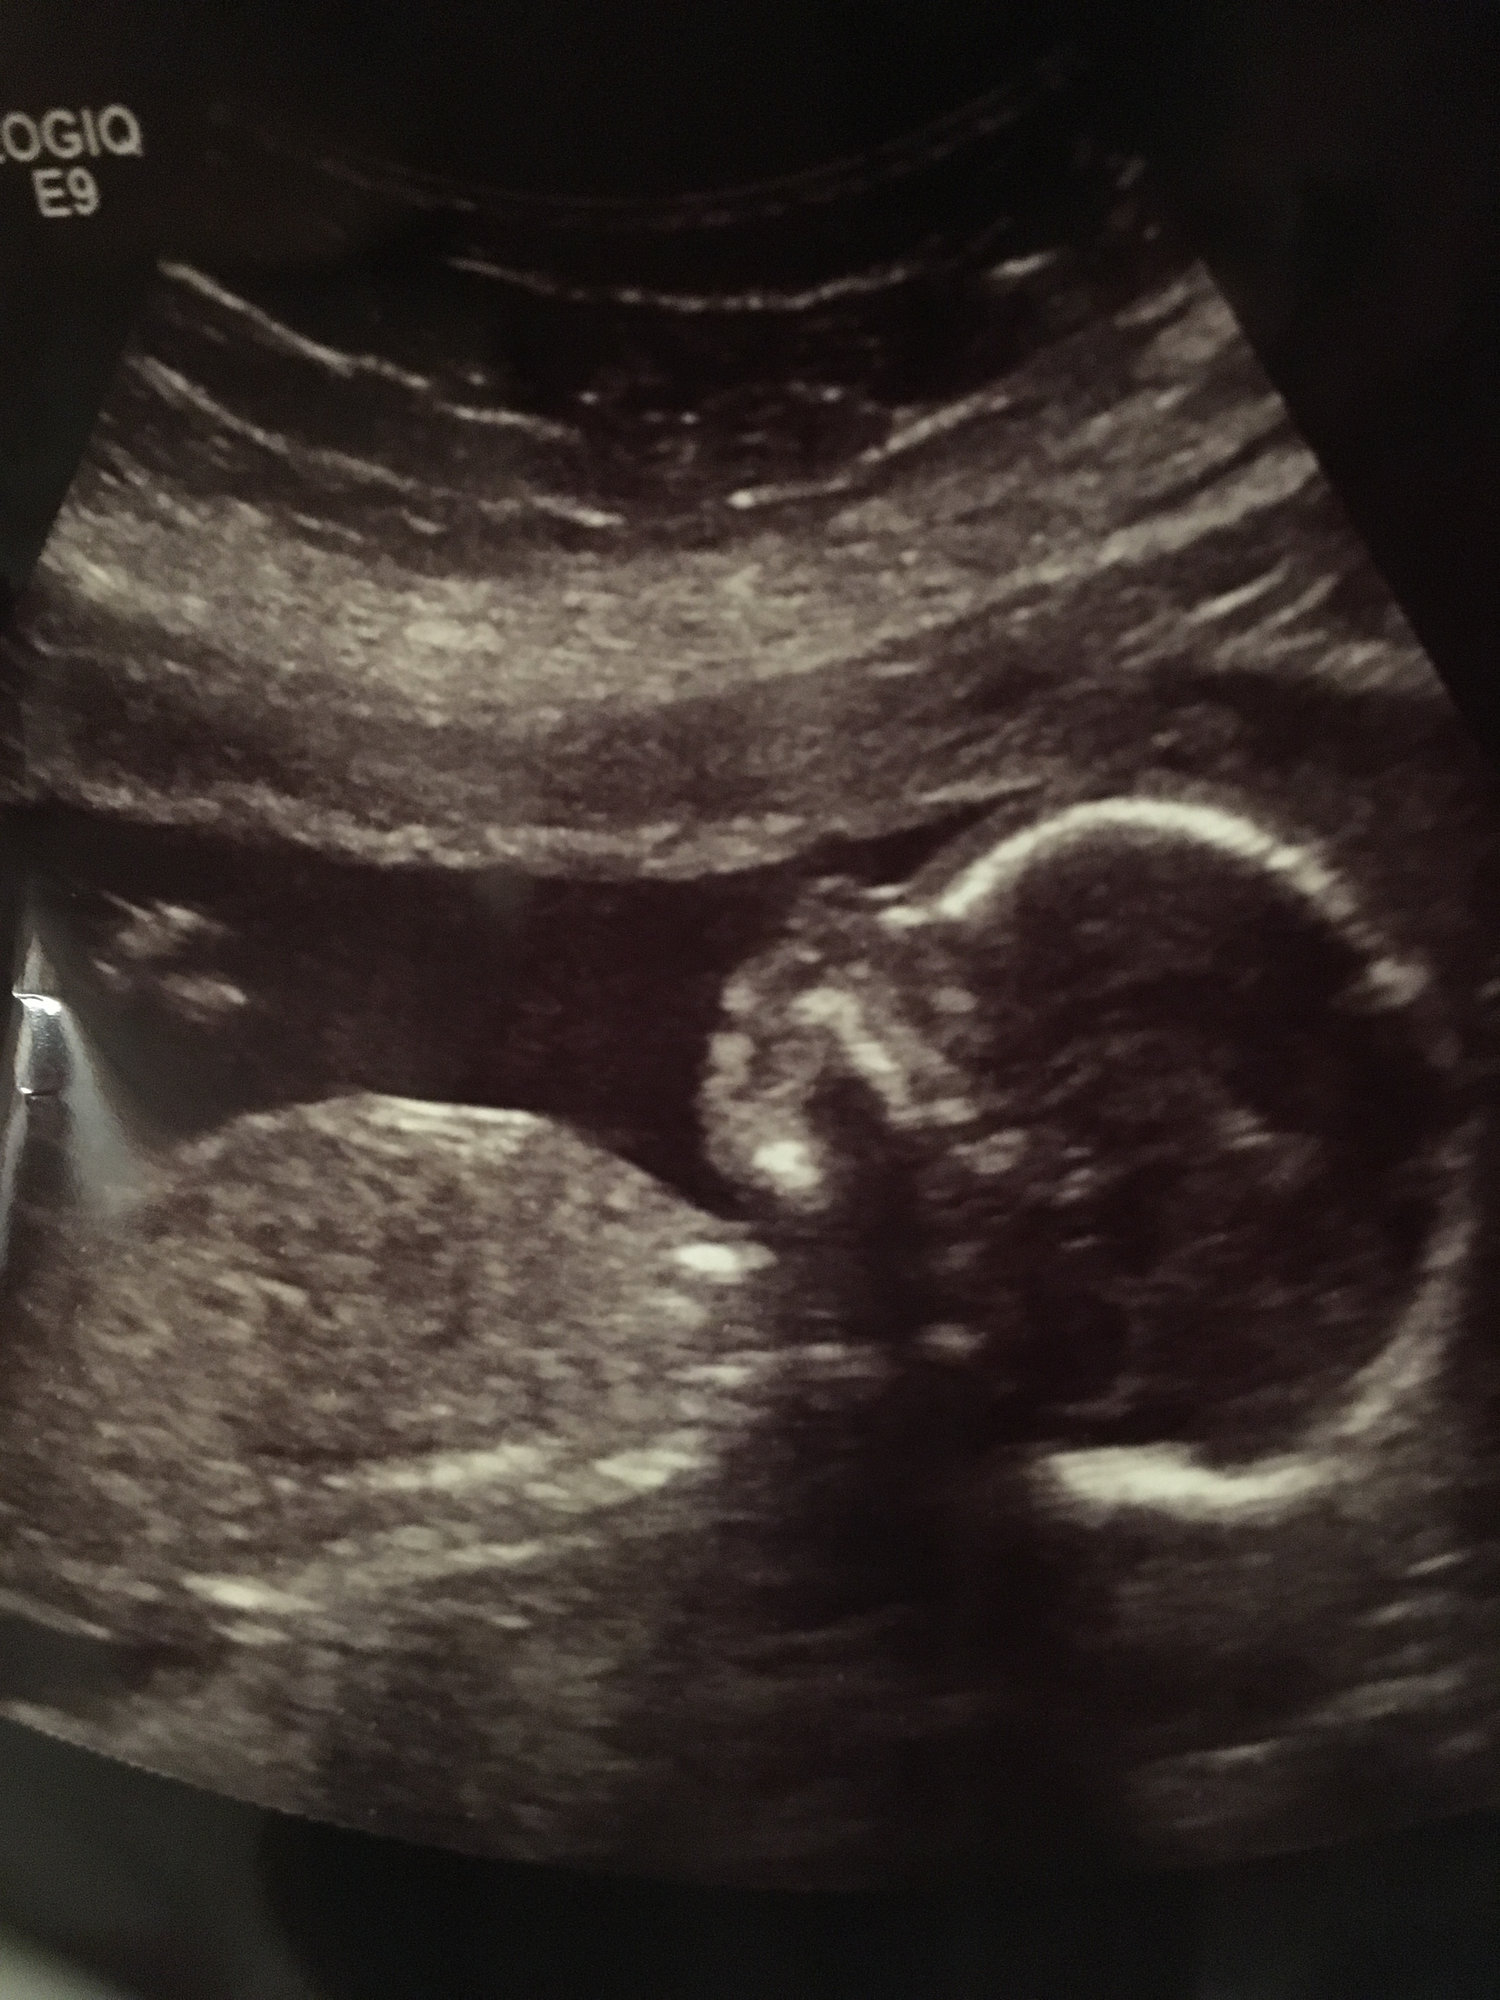

Any appointments? Questions? Had one yesterday. Saw fingers and toes, heartbeat and wiggles. Finally heard the heartbeat on the doppler!